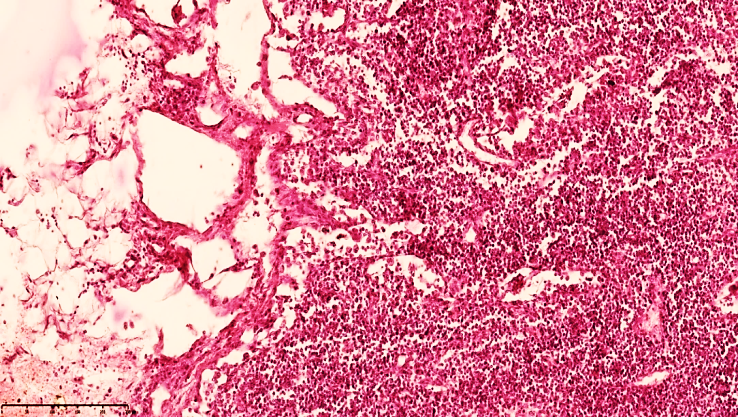

Microscopic examination of regional lymph nodes in infants who died of peritonitis at 28 days of age revealed that the immature medullary and medullary layers were not fully formed, and changes that occurred as a result of severe large-scale purulent and non-purulent inflammation, such as necrotic enterocolitis, before the development of peritonitis led to changes in the lymphatic drainage system in the form of blockage or paralysis.This, in turn, was manifested by a sharp tightening of the capsule in the mesenteric lymph nodes of 28-day-old infants, a sharp expansion of the subcapsular spaces, which were significantly enlarged. In particular, in the development of peritonitis, a sharp decrease in the function of lymphatic drainage mainly leads to the accumulation of exudate fluid in the abdominal cavity. Hyperproduction of mesothelial cells and the formation of multifocal desquamation foci, many erosive foci were also detected in the visceral sheets.In the mesenteric lymphatic vessels, a sharp slowdown in the drainage function of lymphostasis is observed, which is explained by the expansion of the vessels and the increase in size of the fluid accumulated due to plasmarrhagia in the regional lymph nodes. As a result, the capsules of the lymph nodes are stretched, the subcapsular spaces expand, and lymphostasis develops. Eosinophilic inclusions of varying degrees of light and dark staining in the cortex and medulla of the lymph node: cellular components, various tissue parts with destructive changes were detected. The lymph nodes have a swollen appearance, the capsule is tense, and the subcapsular spaces are filled with lymphatic fluid (see Figure 1). Secondary lymphoid follicles are not detected, the germinal center is quiet, the location of lymphocytes in the cortical and paracortical areas of the active areas of the lymph nodes is reduced compared to normal, and in the active areas of the cortex, foci of lymphocytes migrating towards the postcapillary venules are detected. In the direction of the cerebral bands of the medulla, it is determined that a swelling appearance in the areas of the lymphatic gate and a variable mixture of lymphocytes and other types of cells (macrophages, dendritic cells, interdigitating cells, fibroblasts, histiocytes, reticulocytes, etc.) are relatively preserved in the areas of the reticulum and trabeculae of the brain bands. | Figure 1. Mesenteric lymph node of a 28-day-old infant with peritonitis. Treated for 10 days. The lymph node capsule is of variable width, the subcapsular space is dilated, and lymphoid follicles are not identified. Small vessels are fully visible. Stained with GE. Size 10x10 |